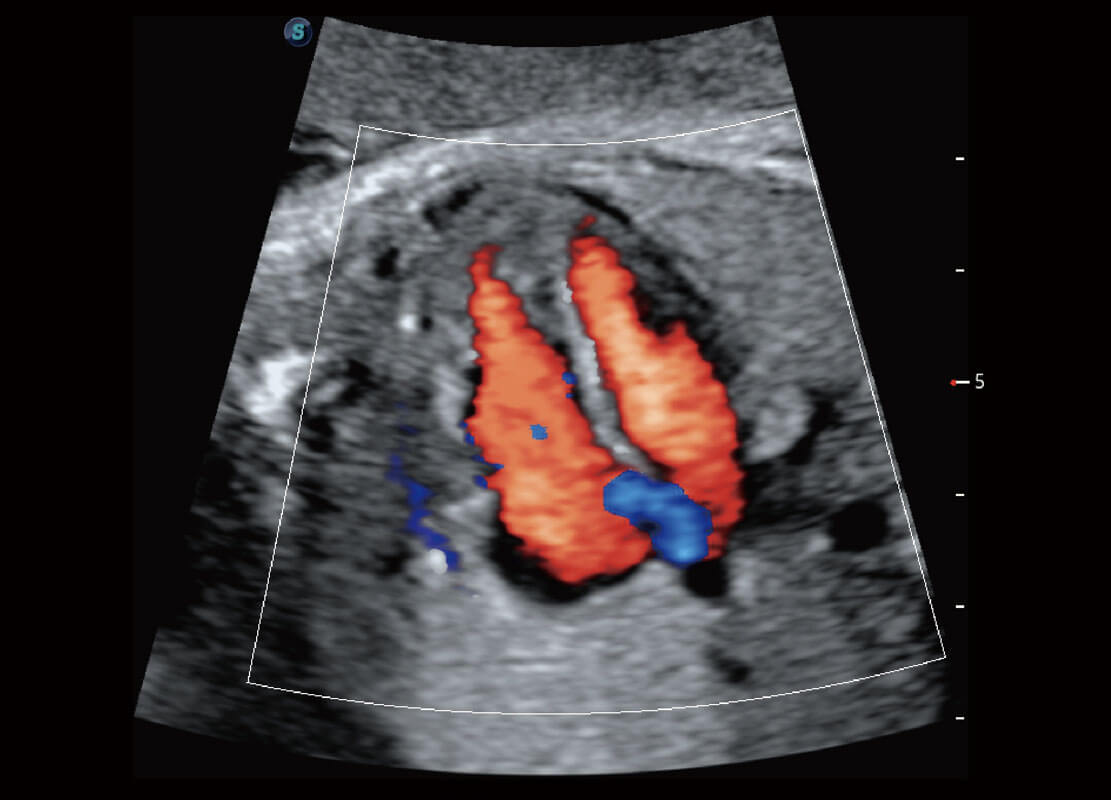

腔内妇科-卵巢

P60优异的图像质量搭载专科探头,在妇科基础疾病的诊断、卵泡生长的监测、输卵管通畅情况的判别等方面为您提供生殖应用方案。